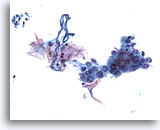

Brossage bronchique

Faible grossissement montrant un groupe de cellules issu d’un carcinome indifférencié à grandes cellules.

20x